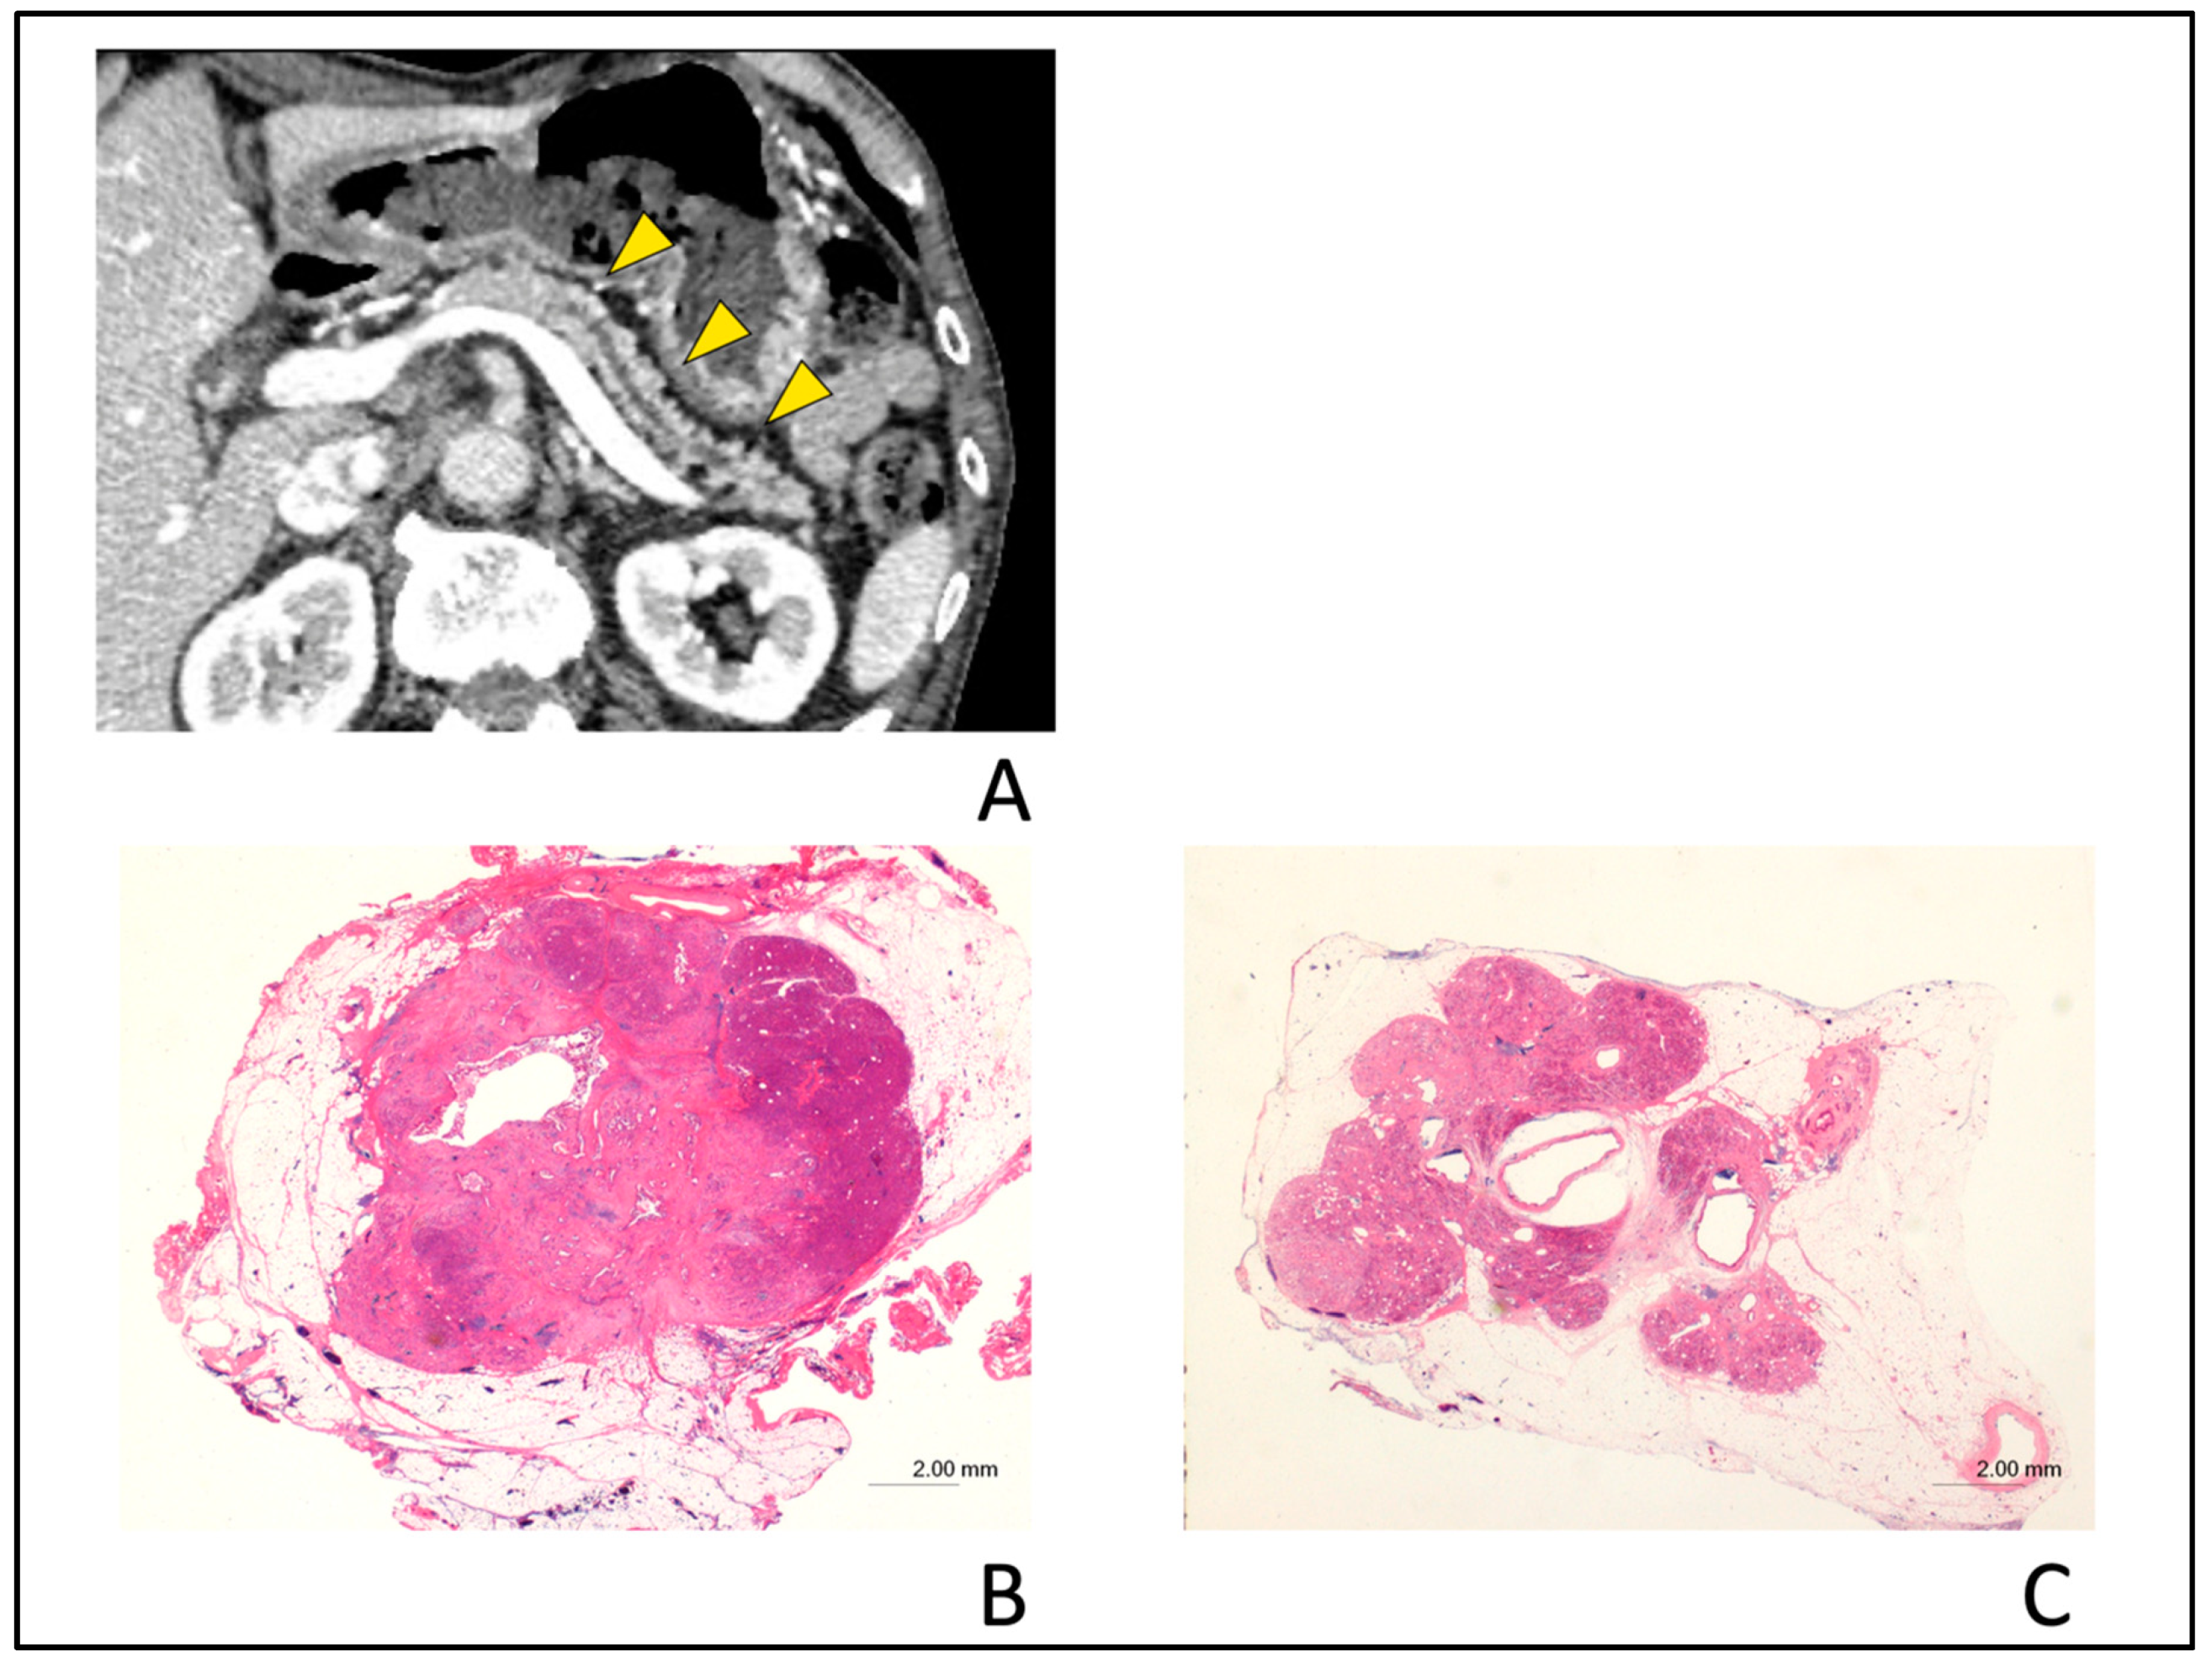

Figure 6.

Typical computed tomography (CT) images showing partial pancreatic parenchymal atrophy (PPA) in an 81-year-old man with stage 0 (carcinoma in situ) pancreatic cancer. Localized main pancreatic duct (MPD) stenosis without tumor lesion in the pancreatic body was detected in CT for further examination of a small cyst in the pancreatic tail. (A); The area exhibiting PPA had an atrophic change corresponding to the distribution of MPD stenosis (yellow arrow head) and defined as localized atrophy compared with the upstream and downstream parenchyma (pink arrow). (B); Hematoxylin and eosin (H&E)-stained resected specimen. Histopathological examination showed high-grade pancreatic intraepithelial neoplasia (PanIN) of the main pancreatic duct (H&E stain, ×20 magnification). (C); Severe atrophy and fibrosis of the pancreatic parenchyma and focal fatty change adjacent to the high-grade PanIN (H&E stain, ×0.5 magnification). (D); Downstream side of pancreatic parenchyma had no atrophic change as compared with Figure 6C (H&E stain, ×0.5 magnification). (E); Upstream side of pancreatic parenchyma had slight fibrosis and focal fatty change as compared with Figure 6C. Acinar cell architecture was maintained (H&E stain, ×1 magnification).